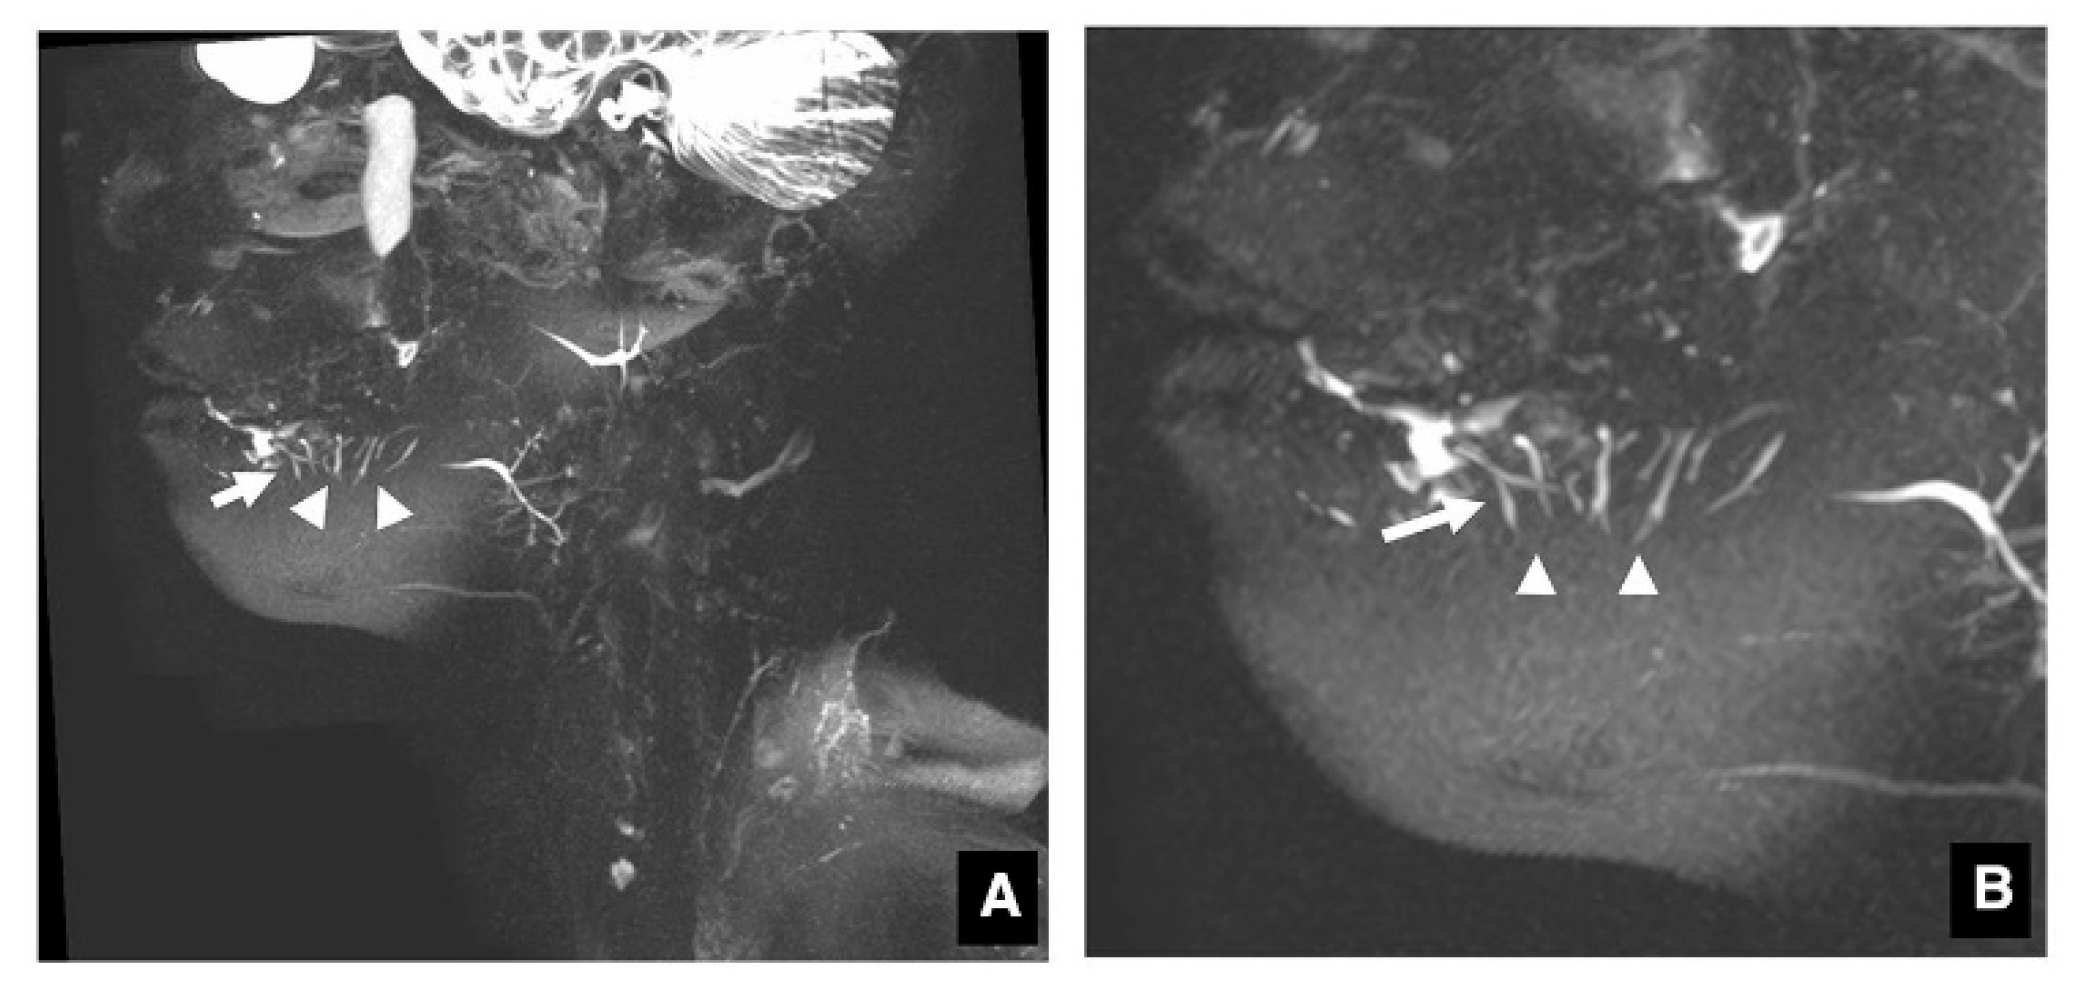

3.1. Visualization of Sublingual Gland Ducts by MR Sialography

3.2. Function of Sublingual Gland Ducts Evaluated by Dynamic MR Sialography